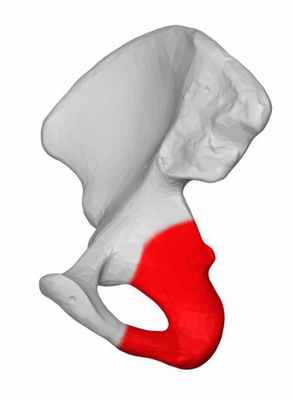

Седалищная кость (лат. os ischii ) — у позвоночных животных парная кость, одна из трёх, образующих при сращении тазовую кость.

По своему строению седалищная кость — губчатая кость, па́рная; левая и правая седалищные кости участвуют в образовании задненижней стенки таза и воспринимает основную нагрузку верхней части тела при сидении человека на ягодицах.

- тела седалищной кости (лат. corpus ossis ischii ): участвует в образовании вертлужной впадины[en] (лат. acetabulum ) образовании тазобедренного сустава, верхней части запирательного отверстия[en] (лат. foramen obturatum ). На задней поверхности имеется выступ — седалищная ость (лат. spina ischiadica ), над которой имеется большая седалищная вырезка (лат. incisura ischiadica major ), под ней — малая седалищная вырезка (лат. incisura ischiadica minor ). Тело кости книзу переходит в ветвь седалищной кости, спереди соединяется с телом лобковой кости, кверху с телом (спереди) и крылом подвздошной кости (сзади);

- ветви седалищной кости (лат. ramus ossis ischii ): участвует в образовании задненижней части запирательного отверстия, на передневерхней поверхности имеется задний запирательный бугорок (лат. tuberculum obturatorium posterius ), на задненижней — седалищный бугор (лат. tuber ischiadicum ). Нижнемедиальная часть соединяется с нижней ветвью лобковой кости (лат. ramus inferior ossis pubis ).

Седалищный бугор правой седалищной кости

Седалищная ость правой седалищной кости

Запирательное отверстие правой тазовой кости